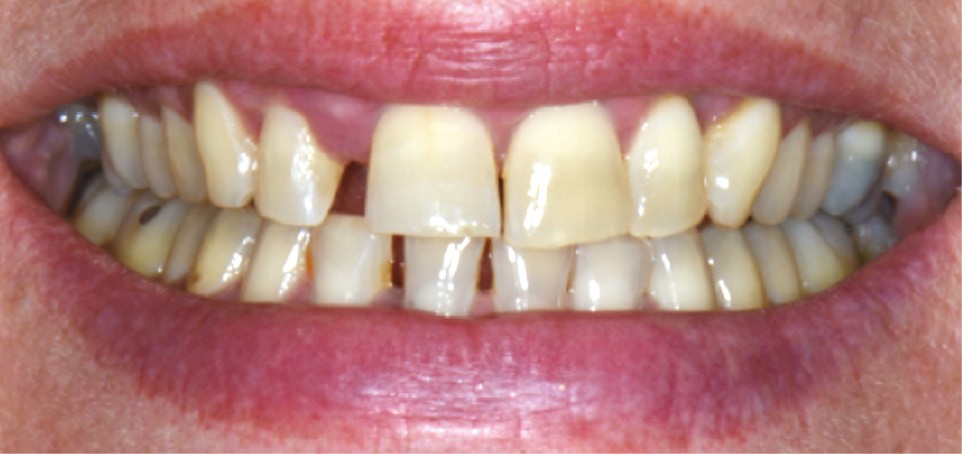

La migration dentaire pathologique est un déplacement dentaire provoqué lorsque l’équilibre entre les forces qui maintiennent la position physiologique de la dent et les forces qui tendent à la déplacer est rompu [1]. Selon la quantité de perte d’attache, de simples forces occlusales ou la poussée linguale lors de la déglutition suffisent à déplacer la dent.

La MDP est une complication fréquente des parodontites et parfois l’un de ses premiers signes cliniques visibles par le patient et son entourage. Sa prévalence est de 30 à 55 % chez les patients atteints de parodontites modérées et sévères [2].

La MDP est dépendante de l’axe des forces appliquées à la dent. Ces forces peuvent ainsi conduire à des déplacements horizontaux, des versions (basculement par rotation) et/ou des égressions/extrusions (déplacement vertical seul, souvent retrouvé lors de la perte de dent antagoniste).

Des combinaisons de mouvements sont le plus souvent retrouvées, notamment lors de la perte du calage postérieur : déplacement horizontal et vertical, migration « en éventail ».

L’étiologie des MDP est complexe et souvent multifactorielle. L’inflammation du parodonte (et son élargissement desmodontal), mais surtout la perte du ligament et de l’os alvéolaire dans lequel il est attaché, diminuent la solidité de l’ancrage et la résistance de la dent à l’impact des forces en présence :